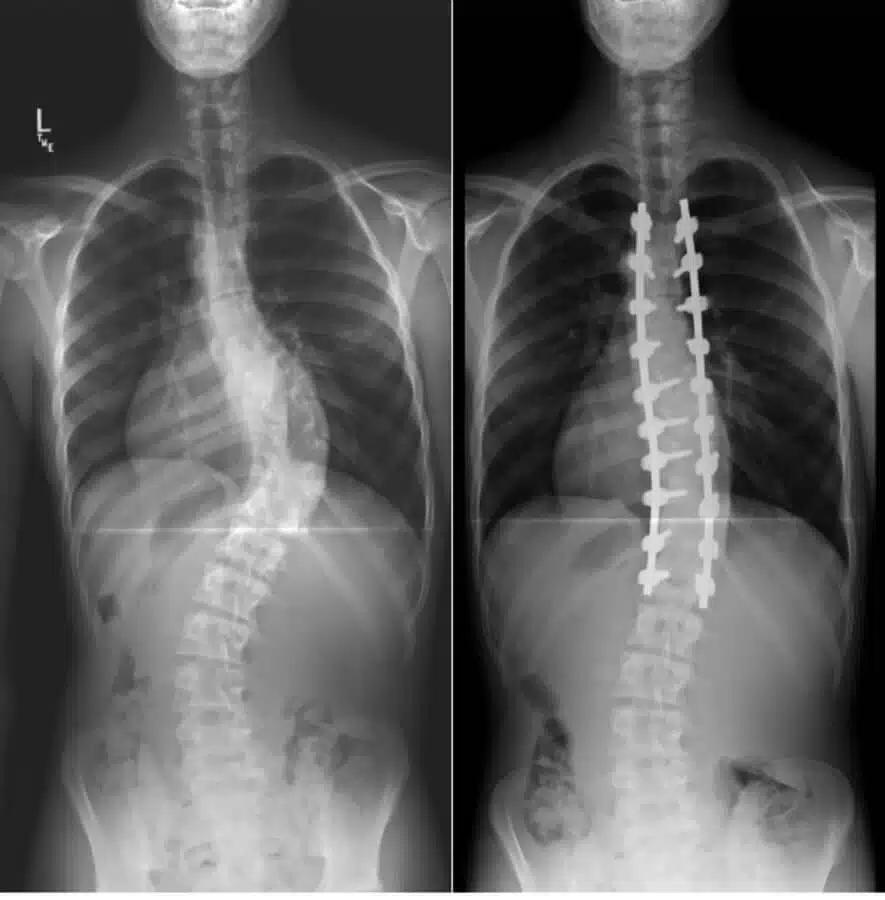

- تصحيح الانحناء الجانبي للعمود الفقري مثل الجنف (انحراف العمود الفقري).